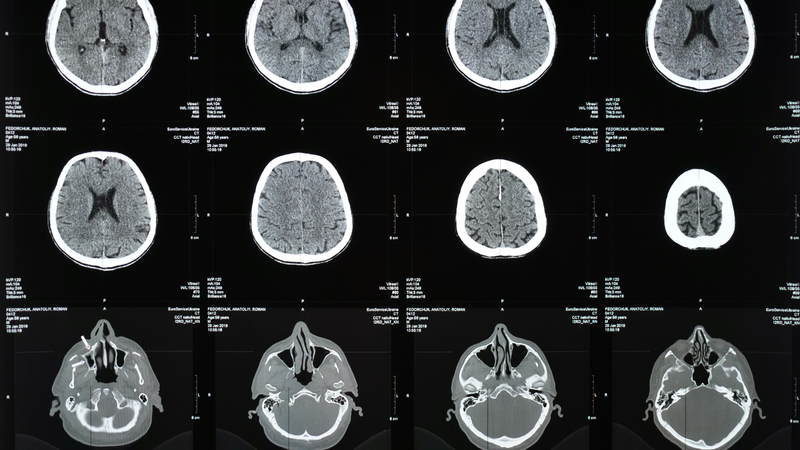

Nhóm nghiên cứu này, do Tiến sĩ Frederick H. Epstein, thuộc Khoa Kỹ thuật Sinh học của Đại học Virginia dẫn dắt, đang nỗ lực sử dụng MRI để đánh giá thành phần của mô mỡ xung quanh tim, được gọi là mỡ màng ngoài tim (epicardial adipose tissue). Phương pháp này có thể giúp bác sĩ xác định các bệnh nhân có nguy cơ cao mắc các bệnh tim mạch nguy hiểm như bệnh mạch vành, rối loạn nhịp tim (như rung nhĩ) và suy tim, đồng thời dự đoán khả năng đáp ứng với các phương pháp điều trị. Những thử nghiệm ban đầu với kỹ thuật này đã cho thấy những tín hiệu tích cực, cho thấy đây có thể là công cụ mạnh mẽ giúp cải thiện chất lượng chăm sóc bệnh nhân.

Mặc dù phương pháp MRI mang lại nhiều triển vọng, việc nghiên cứu và phát triển nó không phải là một công việc đơn giản. Một trong những thách thức lớn nhất là sự chuyển động không ngừng của tim và phổi, điều này khiến cho việc chụp ảnh mỡ quanh tim trở nên khó khăn. Tuy nhiên, nhờ vào sự phát triển của các phương pháp hình ảnh tiên tiến, nhóm nghiên cứu UVA đã có thể thu được các hình ảnh rõ ràng trong thời gian ngắn, chỉ trong một lần giữ hơi thở.

Tiến sĩ Epstein cho biết: “Khả năng thực hiện các phép đo này trong mô mỡ ngoài tim yêu cầu sử dụng các phương pháp tính toán tiên tiến, giúp tách ra dấu hiệu đặc trưng của axit béo bão hòa từ tín hiệu tổng thể.” Bằng cách này, nhóm nghiên cứu đã có thể vượt qua được những khó khăn kỹ thuật để thu thập những dữ liệu quan trọng. Đặc biệt, Jack Echols, một sinh viên tốt nghiệp ngành kỹ thuật sinh học trong nhóm của Tiến sĩ Epstein, đã có những đóng góp xuất sắc trong việc phát triển các phương pháp này.

Sau những thử nghiệm ban đầu, nhóm nghiên cứu UVA đã tiến hành thử nghiệm công nghệ MRI mới này trên một số bệnh nhân. Kết quả cho thấy, ở những bệnh nhân béo phì và từng bị nhồi máu cơ tim, mỡ quanh tim chứa một lượng lớn axit béo bão hòa. Điều này gợi ý rằng phương pháp MRI mới có thể trở thành một công cụ hữu ích trong việc phát hiện các bệnh nhân có nguy cơ cao và dự đoán kết quả điều trị của họ.